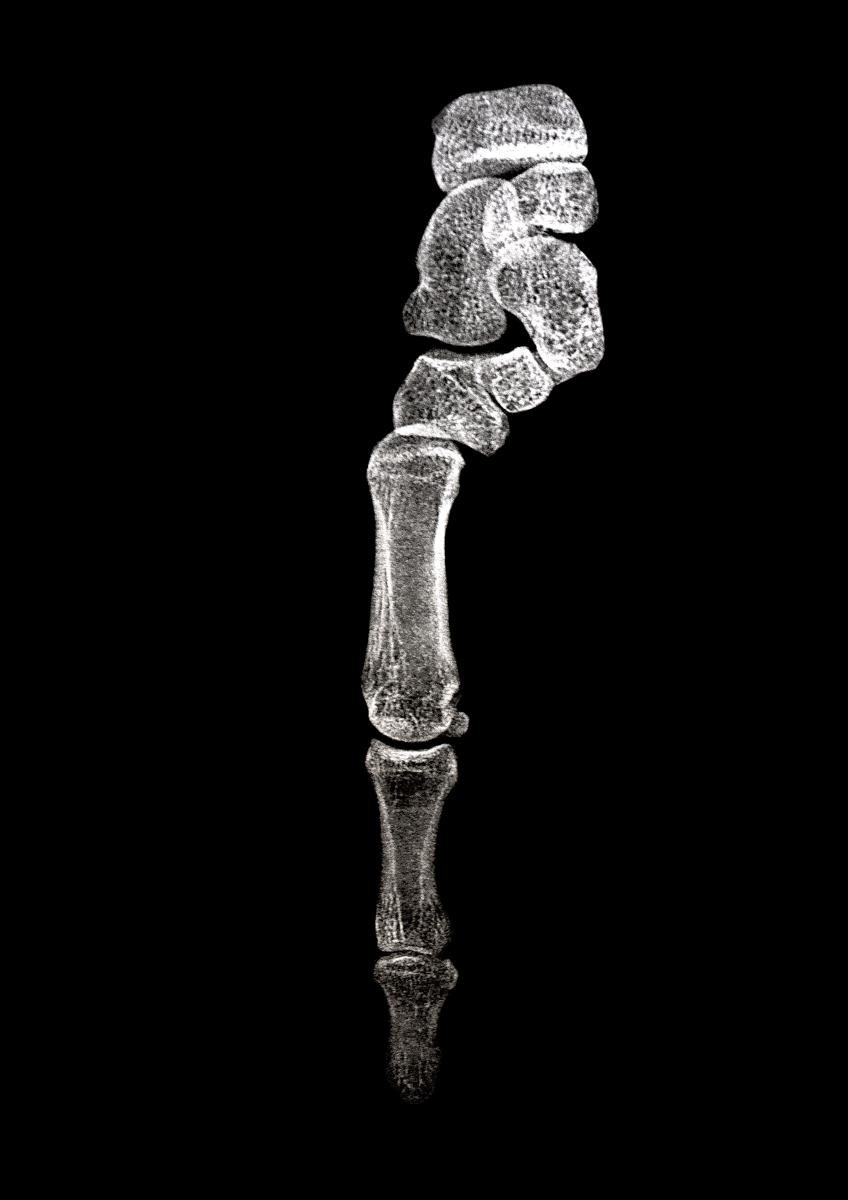

SURFACES SENSIBLES — À la frontière de l'autoportrait, "Surfaces sensibles" retranscrit une partie de ma réalité et brouille les limites entre l'intime anatomique et l'émotionnel.

La science produit les images les plus concrètes et les plus neutres pour illustrer les affects. Pourtant, par leur froideur et leur distance, elles sont les moins aptes à témoigner des émotions. Chaque radiographie, scanner, IRM correspond à une douleur ou à un mal-être spécifique.

Depuis peu, ces images ne sont plus seulement des réminiscences de douleurs passées, mais également des matériaux bruts inspirants pour ma pratique photographique. À partir des radios originelles, j'ai utilisé plusieurs techniques telles que la superposition et le tirage argentique dans le but de me rapprocher d'une perception alternative de ce corps irradié.